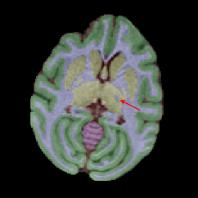

Non-human primates (NHPs) serve as critical models for understanding human brain function and neurological disorders due to their close evolutionary relationship with humans. Accurate brain tissue segmentation in NHPs is critical for understanding neurological disorders, but challenging due to the scarcity of annotated NHP brain MRI datasets, the small size of the NHP brain, the limited resolution of available imaging data and the anatomical differences between human and NHP brains. To address these challenges, we propose a novel approach utilizing STU-Net with transfer learning to leverage knowledge transferred from human brain MRI data to enhance segmentation accuracy in the NHP brain MRI, particularly when training data is limited. The combination of STU-Net and transfer learning effectively delineates complex tissue boundaries and captures fine anatomical details specific to NHP brains. Notably, our method demonstrated improvement in segmenting small subcortical structures such as putamen and thalamus that are challenging to resolve with limited spatial resolution and tissue contrast, and achieved DSC of over 0.88, IoU over 0.8 and HD95 under 7. This study introduces a robust method for multi-class brain tissue segmentation in NHPs, potentially accelerating research in evolutionary neuroscience and preclinical studies of neurological disorders relevant to human health.